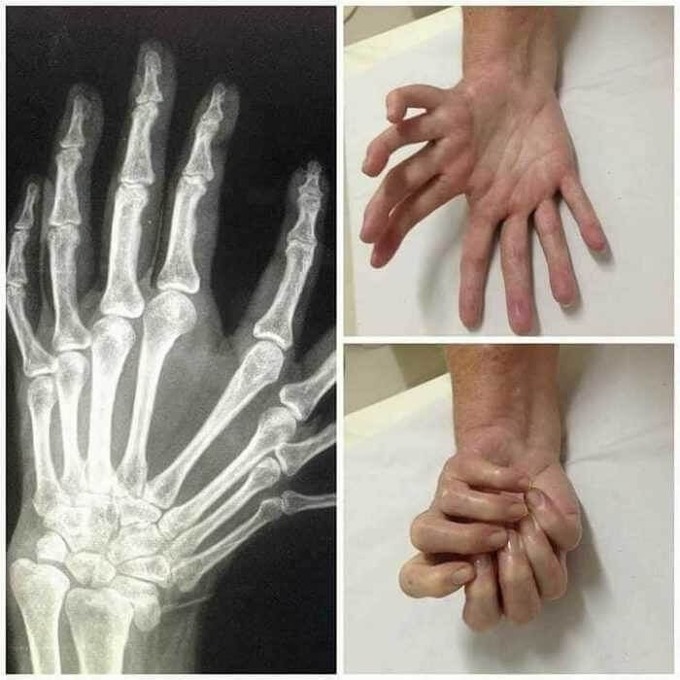

多指症は遺伝することもあれば、個人に散発的に発生することもあります。家族性多指症として知られる家族内で遺伝することもあり、遺伝子変異によって発生する場合もあります🖖🤔

1000人に一人くらいはある割とメジャーな奇形なんだよね